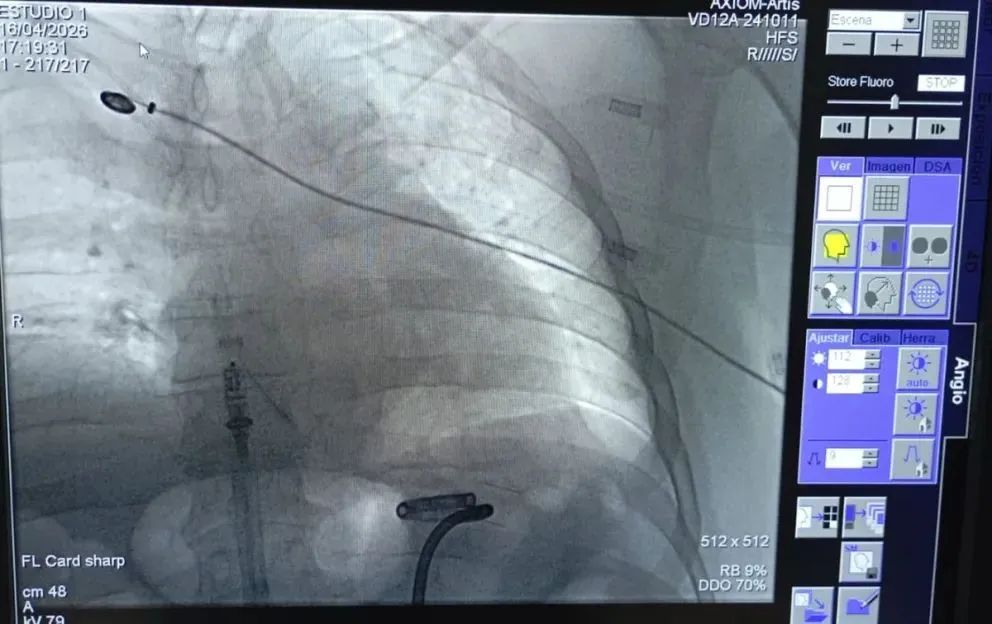

Colocaron en Río Negro el marcapasos más pequeño del mundo

Es 10 veces más diminuto que los dispositivos convencionales. La intervención se concretó en la Clínica Viedma.

Durante una intervención de 40 minutos, un paciente recibió un marcapasos de altísima tecnología que le permitirá hacer vida común. El procedimiento fue realizado por el equipo del Servicio de Electrofisiología de la Unidad de Cardiología de Clínica Viedma.

Estuvo encabezada por Martín Calvelo, jefe de Cardiología de Clínica Viedma y con  la supervisión de Ariel Estévez, médico proctor especializado la implementación de estas cirugías perteneciente a la empresa Medtronic, proveedora deldispositivo, denominado Micra AV2, que es 10 veces más pequeño que uno convencional, dura un 40 % más y evita complicaciones al paciente.

Lo recibió en ese instituto médico, un paciente de 56 años quien presentaba infecciones de catéteres a repetición, lo que impedía la implantación de un marcapasos convencional por la vía tradicional de la parte superior del cuerpo.

Se trata de un dispositivo de vanguardia diseñado por Medtronic (empresa líder mundial en tecnología médica), que da soluciones efectivas mediante procedimientos mínimamente invasivos, que permite la eliminación de complicaciones relacionadas con la manipulación de los cables para su conexión y supone una mejora por su reducido tamaño y la eliminación del bolsillo subcutáneo donde se depositan los marcapasos convencionales, dispositivos implantables utilizados para el tratamiento de personas con determinadas alteraciones del ritmo cardíaco.

Este marcapasos mide apenas dos centímetros de longitud, un 93% más pequeño que los modelos tradicionales, con un tamaño aproximado de 2,5 centímetros y un peso de tan solo dos gramos, siendo reconocido en el mundo.